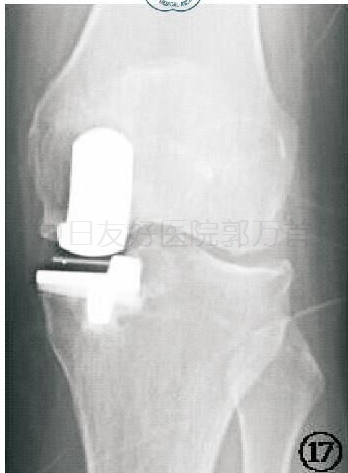

X线片九:并发症之活动垫片脱位

X线检查可以发现衬垫移位的位置,同时还可能提示造成移位的原因,如骨赘、骨水泥残留、金属假体移位等。